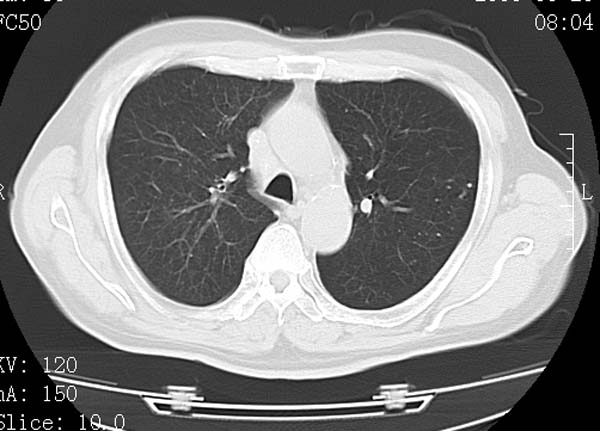

以下是引用守望可可西里在2008-6-24 1:11:00的发言:[br][br] 考虑为周围型肺癌:[br] 1.分叶结节,形态极不规则,蟹足样伸展的恶性浸润特征比较明确。[br] 2.磨玻璃影中由多个更高密度小结节聚集呈梅花瓣样。[br] 3.局部胸膜凹陷征比较明确。[br][br] 另:纵隔胸膜明显增厚、粘连。

以下是引用zjzjr在2008-6-24 11:19:00的发言:[br]支持左下肺周围型肺癌伴右肺转移,纵隔淋巴结转移,心包积液.

以下是引用zhangling在2008-6-24 14:56:00的发言:[br]我们科室意见报告为[br][br]1考虑左下肺周围型肺癌[br]2右肺小结节考虑转移瘤,纵隔淋巴结转移[br]3心包积液. [br] 各位老师分析的相当好 谢意[br]